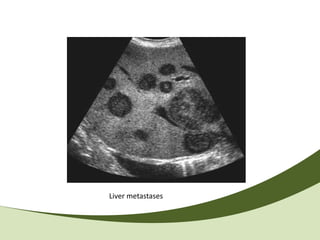

Liver metastases